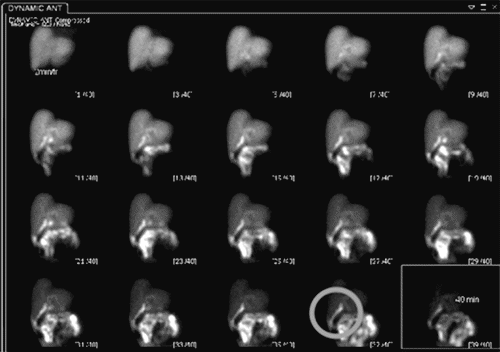

While the patient reported initial relief of symptoms within 48 hours of the initial procedure, he experienced a recurrence of nausea, distension, and abdominal pain. Post paracentesis, CT imaging of the abdomen pelvis failed to show extravasation of oral contrast from viscera (Figure 1) but revealed a contracted gallbladder and re-accumulation of ascites. A hepatobiliary iminodiacetic acid (HIDA) scan showed a biliary leak from the region of the gallbladder fossa (Figure 2). Magnetic resonance cholangiopancreatography showed recurrent ascites but no biliary obstruction (Figure 3). No traumatic injuries were identified on the initial imaging. Repeat paracentesis yielded one liter of bilious fluid, again with a resolution of symptoms.

Figure 3. Magnetic Resonance Cholangiopancreatography Showing Ascites (arrow). Published with Permission